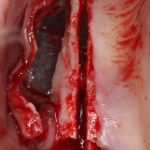

Откроем область операции и посмотрим, что там:

Вроде как, всё неплохо. Наверное, можно поставить имплантаты?

При этом, я хотел бы обратить ваше внимание на один важный момент. То, с чем вы сейчас работаете — не кость, в привычном нам гистолого-физиологическом понимании. Это костная мозоль вперемежку с графтом. Её свойства довольно сильно отличаются от того, что мы привыкли называть костной тканью. Поэтому при установке имплантатов соблюдайте максимальную осторожность и щадящий режим. Никаких диких торков, усилий, больших переходов между размерами фрез допускать нельзя. Будьте аккуратны.

Иначе, кривокосячной имплантацией вы можете испортить даже мастерски проведенную остеопластическую операцию.